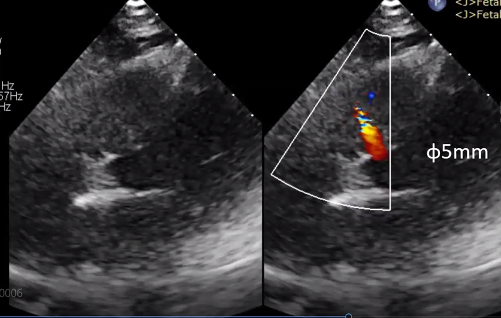

经查抄诊断为膜部VSD,术前超声丈量VSD缺损直径为5mm,轻度左心室容量超负荷,左心室舒张末期内径51mm。

(图:术前超声)